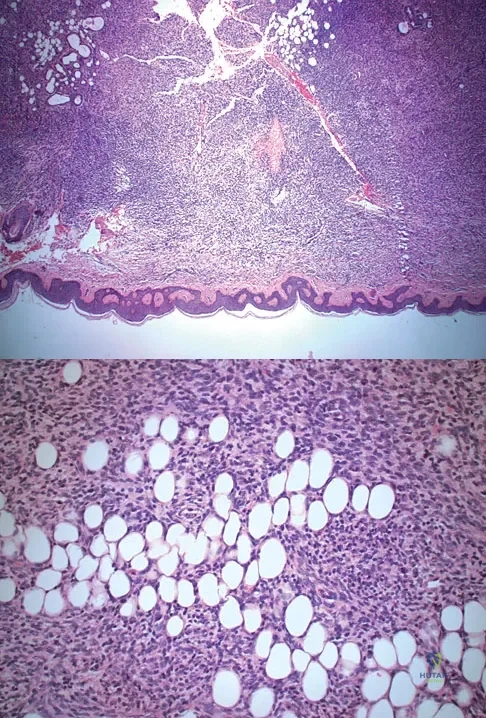

A 58-year-old woman has had a painless periscapular mass for the past year. An MRI scan and biopsy specimen are shown in Figures 4a and 4b. What is the most likely diagnosis?

Elastofibroma is a rare tumor that most commonly occurs in adults who are older than age 55 years. The lesions usually grow between the chest wall and the scapula, and 10% are bilateral. Histologic analysis shows that they are composed of equal amounts of elastin and collagen with occasional fibroblasts. Briccoli A, Casadei R, Di Renzo M, Favale L, Bacchini P, Bertoni F: Elastofibroma dorsi. Surg Today 2000;30:147-152.